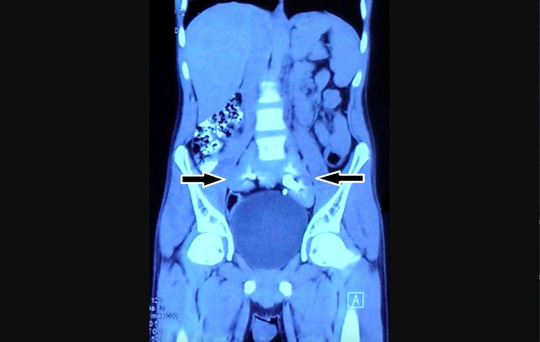

Cấu trúc tròn nhỏ giữa 2 mũi tên là quả thận bị hợp nhất của nam bệnh nhân - ảnh: BMJ Case Report

Thay vào đó, phía trên bàng quang của nam thanh niên có một cấu trúc kỳ lạ trông như một chiếc đĩa mà các bác sĩ điều trị chưa từng thấy trong cơ thể người.

Các bác sĩ đến từ Đại học Y khoa Maulana Azad (New Delhi- Ấn Độ) đã kiểm tra kỹ lưỡng hơn và xác định cấu trúc kỳ lạ kia chính là 1 quả thận. Đó là một dị tật bẩm sinh khi còn trong bào thai. Không chỉ 2 quả thận bị nhập làm 1, nó còn nằm ở vị trí thấp hơn so với thận thông thường.